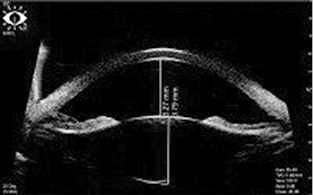

Ультразвуковая биомикроскопия OU: зона патологического контакта пигментного листка радужной оболочки с передней поверхностью хрусталика и цинновыми связками отсутствует (рис. 5, 6). Глубина передней камеры правого глаза 5,14 мм, левого — 5,13 мм.

Рис. 5. Правый глаз, 20-й день после удаления прозрачного хрусталика + установки интраокулярной линзы. 15.09.2018

Рис. 6. Левый глаз, 27-й день после удаления прозрачного хрусталика + установки интраокулярной линзы. 15.09.2018